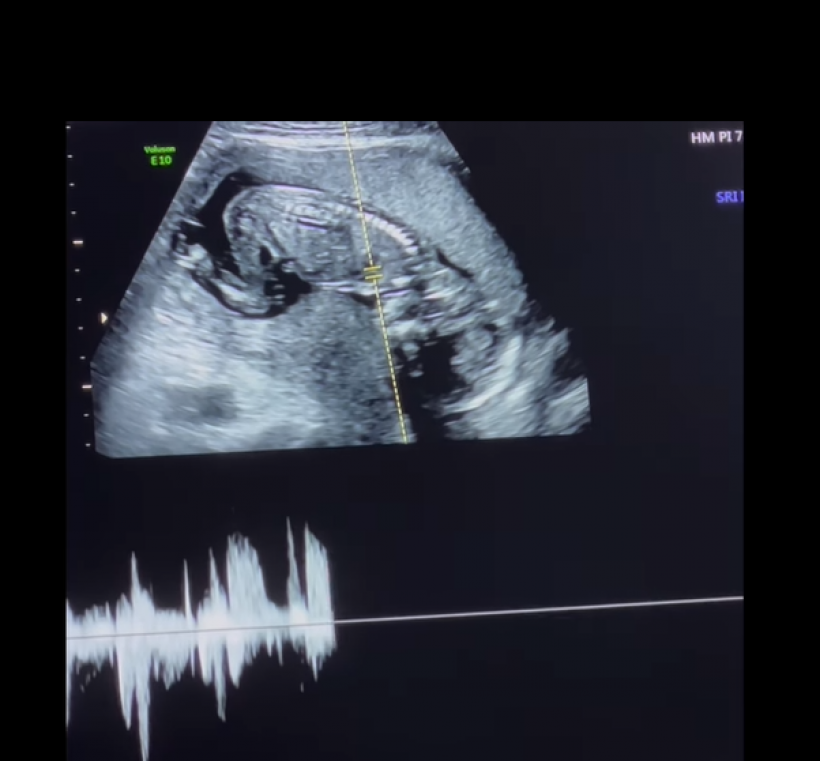

ล่าสุด ดา โพสต์คลิปอัลตร้าซาวด์ พร้อมเเคปชั่นว่า “ขอบคุณคำอวยพรวันเกิดจากทุกคนนะ…ปีนี้อยากจะบอกว่า “ดาได้ของขวัญวันเกิดที่พิเศษที่สุดแล้วนะ” 🎁🥹 THE BEST BIRTHDAY PRESENT EVER! ❤️”

Cr_ig: daendorphine